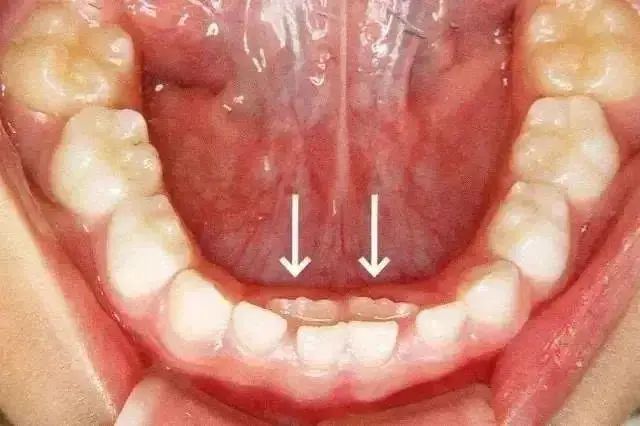

乳牙滞留是指恒牙相继长出,乳牙未能及时脱落。或者恒牙未萌出,保留在恒牙列中。乳牙的脱落与恒牙的生长之间存在着密切的关系。这种情况多见于换牙期的下颌门牙,恒牙长在舌侧,乳牙留于唇侧,出现双排牙。

双排牙一定要拔吗?

很多家长看到孩子“双排牙”后非常着急,要求医生赶紧拔掉,这样对吗?

过早过多的拔牙,容易造成孩子牙颌畸形,拔不拔牙首先要看恒牙萌出的高度,当恒牙只萌出 1/3 或者 2/3 ,且前排牙齿还没有松动的情况下,建议家长先让孩子多吃硬性食物,比如啃苹果、玉米等,促进自然脱落。